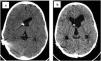

ResultsThe median age at first shunt was two months (0–67). The mean number of shunt revisions before inclusion was three. Shunt removal was attempted in seven patients without success; temporary success was observed in two patients who underwent ETV. Two patients had previous cranial expansions. The mean age at inclusion was 9.1 years (2.7–15.2). After the shunt system was exchanged and upgraded, clinical improvement was observed in 94.4% (17/18) of patients, and radiological improvement was observed in 83.3% (15/18) of patients. The median follow-up was 21 months.